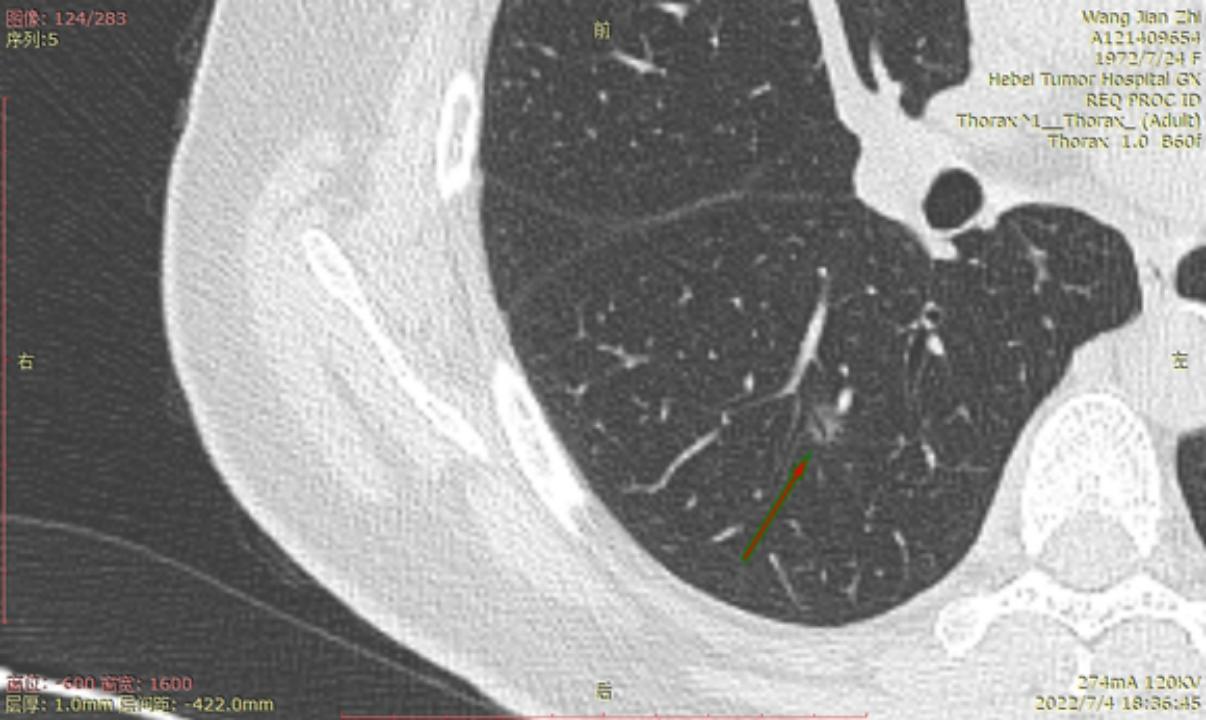

今年6月22号河北省人民医院进行CT检查后,报告双肺多发磨玻璃结节及微小结节以右肺为多,建议六个月后复诊。我于7月3号在河北省四院胸外科就诊,大夫建议复查薄层CT,7月4日CT结果报告示两肺多发结节,部分为磨玻璃密度,建议三个月复查,省四院的主任看了CT后有的建议立即住院手术,有的建议三个月复查,专家意见不一致,后来我看了主任的贴吧,首次发现肺结节先口服莫西沙星,三个月后再复查的贴吧,就没有立刻手术,从7月4日开始口服莫西沙星,现已完成15天疗程。等待复查的这一段时间里,总是担心大的结节已有浸润,请主任给予帮助,看看我的CT,给出我治疗建议,麻烦主任了!

结14

结15

右侧至少5枚以上的微浸润或原位腺癌,大的两枚结节微浸润,建议半年内把右侧5mm以上或者有危险的结节一网打尽。左侧结节还安全,安心随访